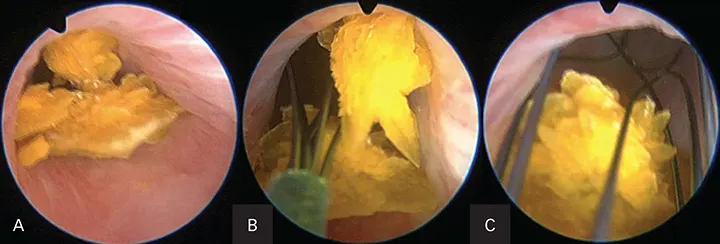

Percutaneous Cystolithotomy

Figure 8. Endoscopic images of a dog with numerous calcium oxalate bladder and urethral stones during percutaneous cystolithotomy. Embedded stones within the urethral lumen (A). Stone basket entrapping the stones (B). Stone basket removing the stones (C).